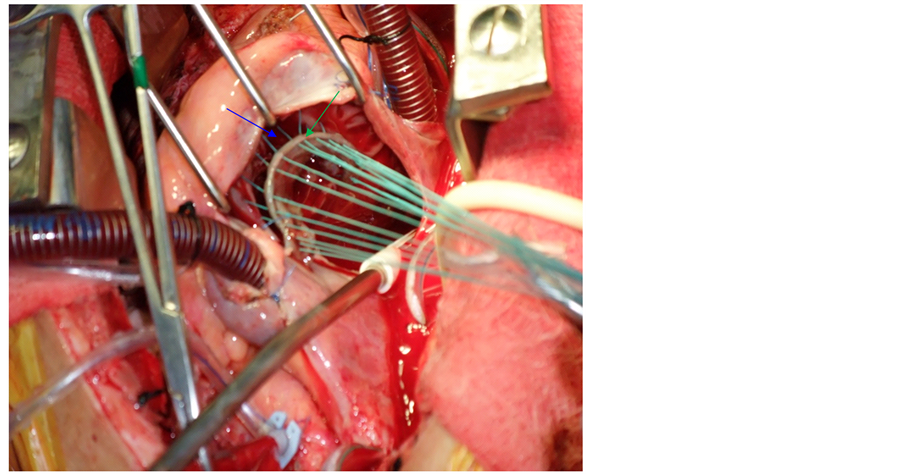

All annuloplasties were performed during concomitant aortic and/or mitral valve surgery with the aorta clamped. Ring annuloplasty was performed by standard operative techniques. For autologous pericardial annuloplasty, we used the technique developed by Chang et al. [4] . We started by harvesting and preparing an autologous pericardial strip (8 to 10 cm in length, 5 to 8 mm in width). The smooth surface was kept upwards and was sutured to the tricuspid annulus with interrupted mattress sutures of 2 - 0 Ethibond suture (Ethicon, Inc, Somerville, NJ). We started from the posteroinferior aspect of the septal leaflet to the anterior septal commissure. The interval between sutures was 2 - 3 mm in the autologous pericardial strip and 5 - 6 mm in the tricuspid annulus. By this way the tricuspid annulus could be shortened (Figure 1). After the procedure, we measured the annular diameter using a valve sizer.

Figure 1. Intraoperative view showing pericardial strip (green arrow) before fixing it to tricuspid annulus (blue arrow).